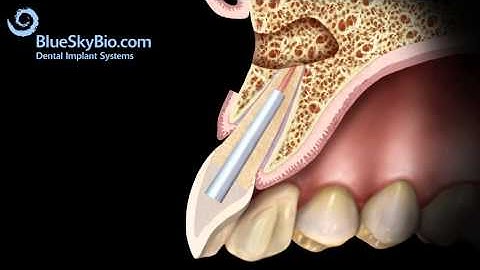

LIVE OPERATION Root Tip Resection with retrograde Filling